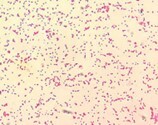

B. cereus var. anthracis gram stain